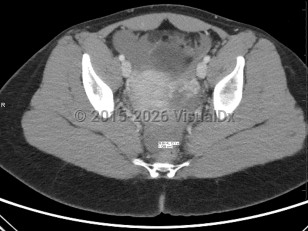

Ruptured ectopic pregnancy can result in intraperitoneal bleeding, uterine hemorrhage, and hemodynamic instability. Development of any of these complications should be considered a surgical emergency and warrants emergent evaluation by a gynecologic surgeon; exploratory laparotomy may be required. Even in the absence of concern for rupture, surgery may be considered, particularly in patients failing or with contraindications to methotrexate, in the setting of heterotopic pregnancy (ectopic pregnancy occurring simultaneously with a viable intrauterine pregnancy; see Look For), or in patients seeking sterilization.